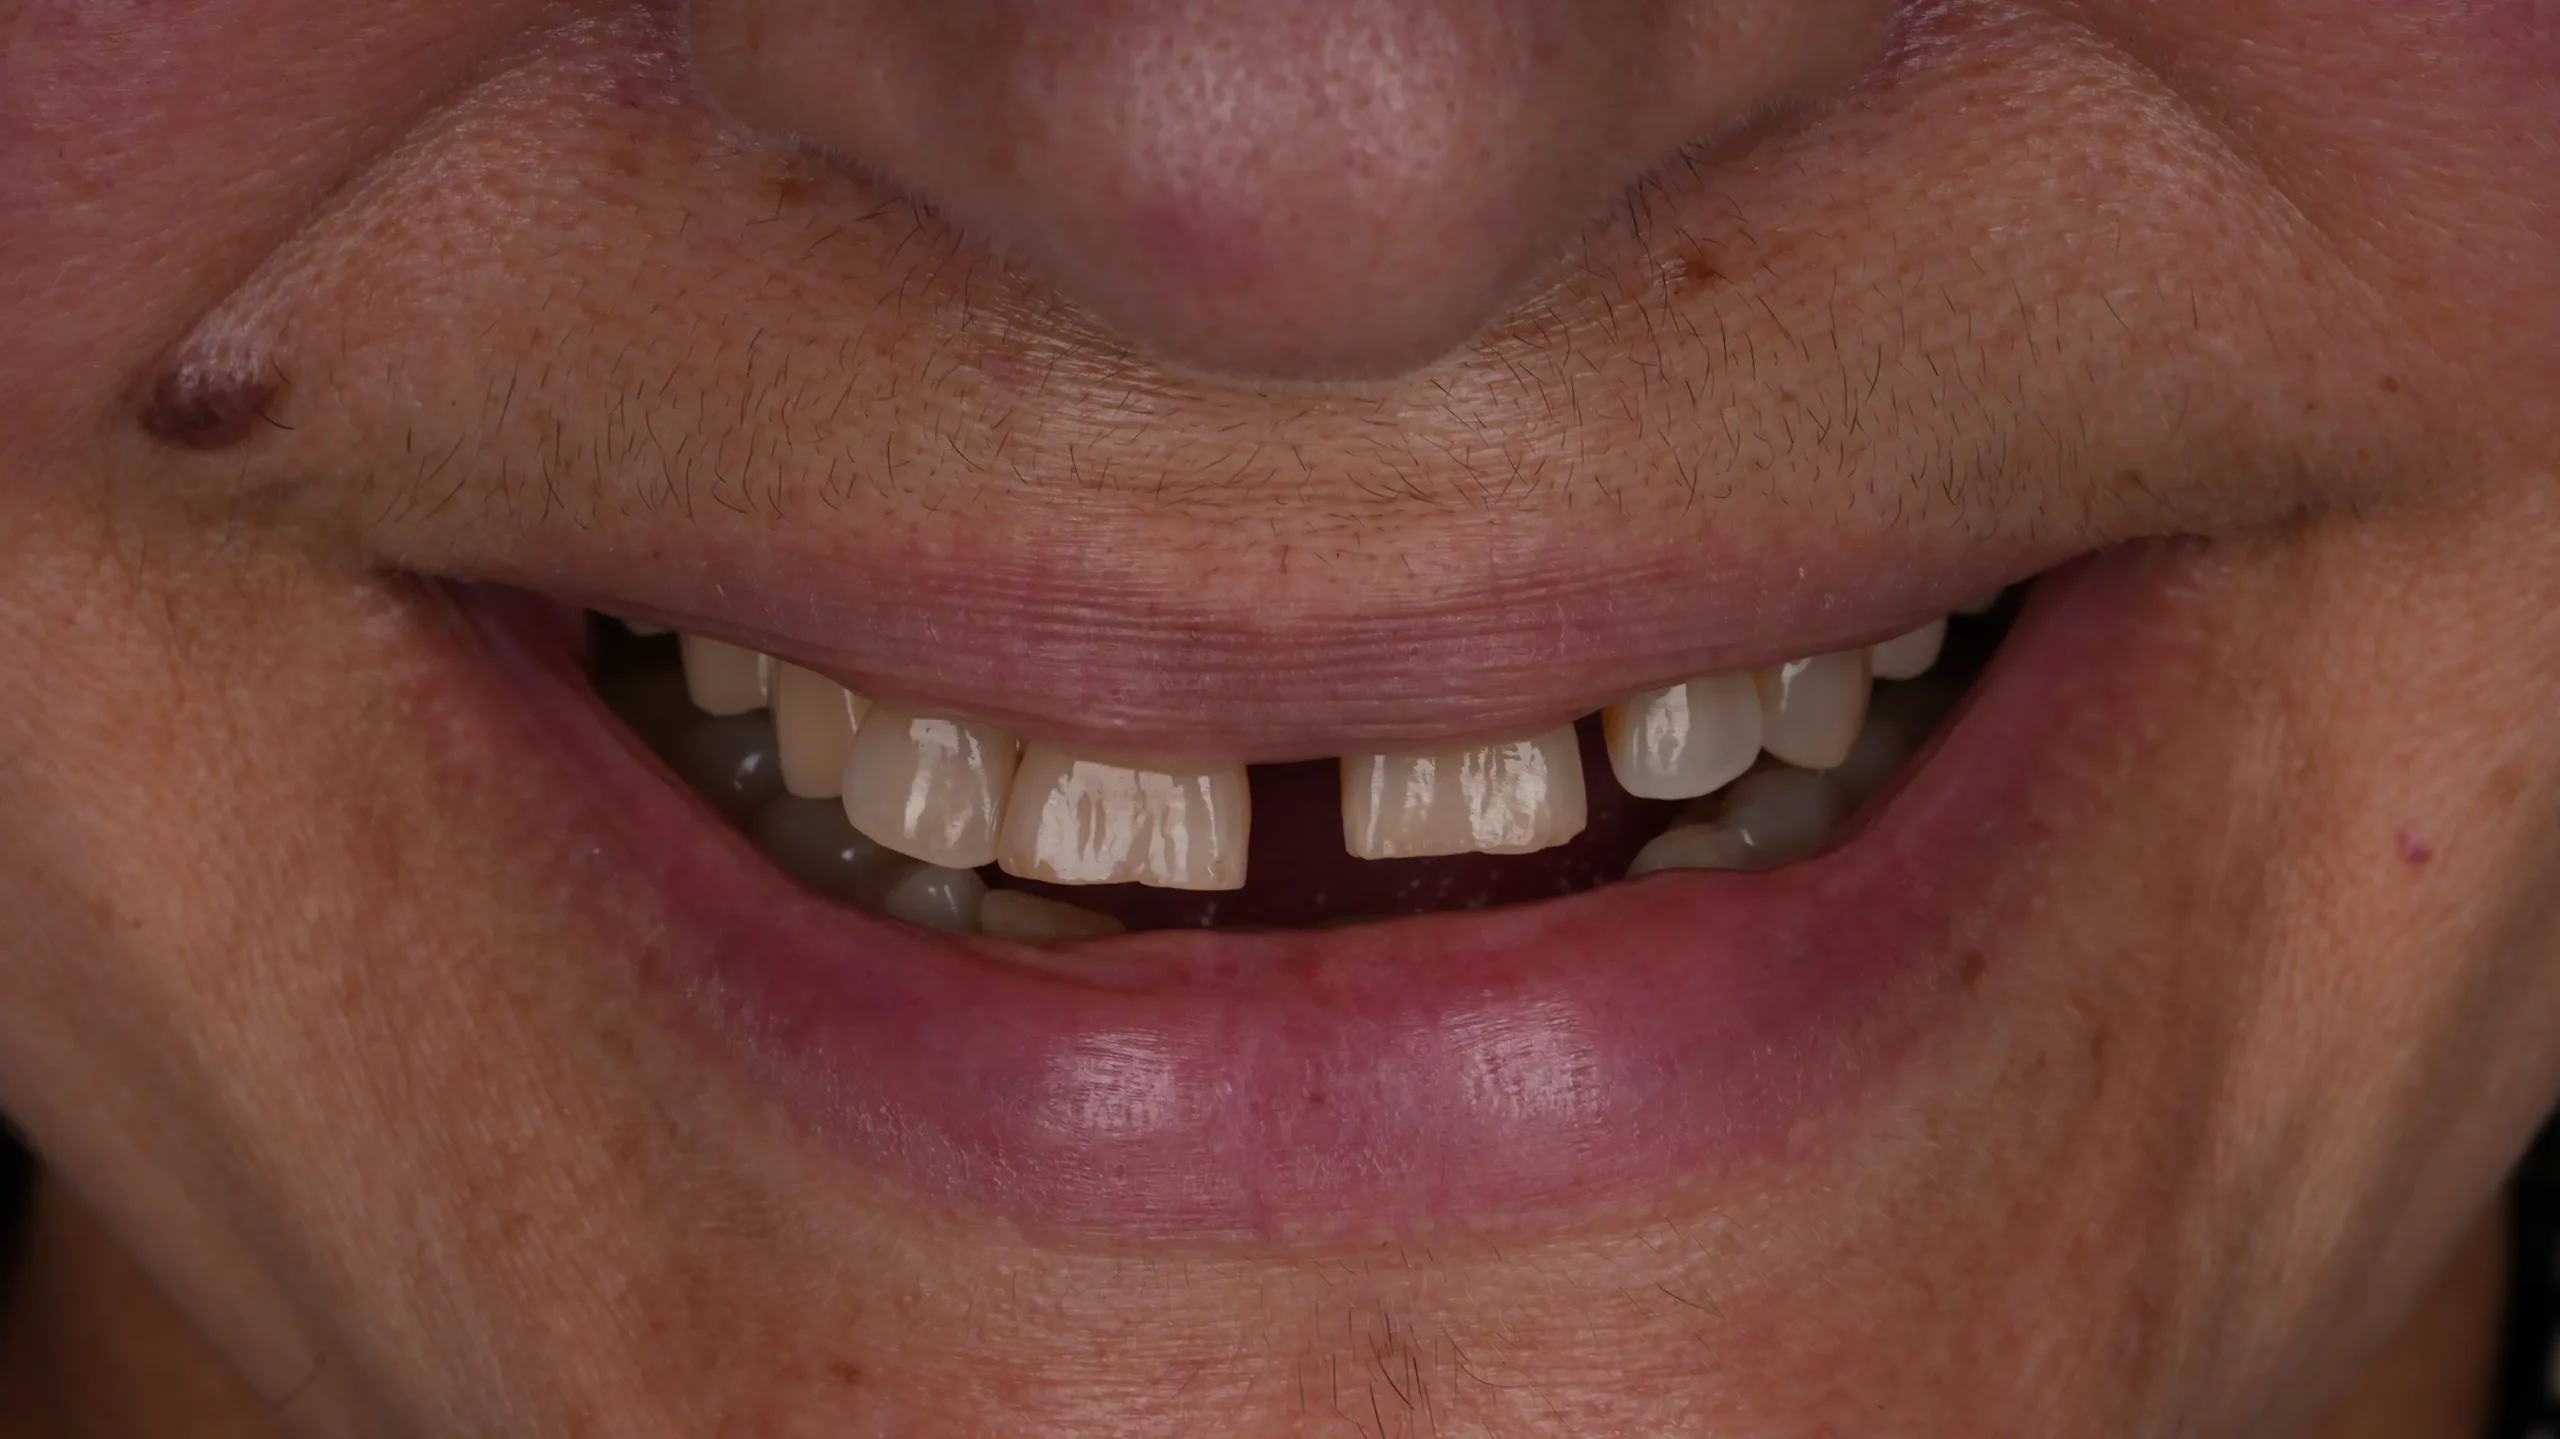

Miriam acudió en busca de ayuda tras un tratamiento fallido que le causaba fuertes dolores y problemas continuos. Su salud bucal se deterioraba y eso afectaba directamente a su autoestima. Hoy, luce una sonrisa sana y segura, símbolo de su recuperación.

5. Dientes oscurecidos

6. Ausencia total de estética dental

Antes del tratamiento Sorriso depois do tratamento

Recuperacion de salud bucodental en ausencia e infecciones, recupercion de la perdida de hueso y tejido blandos, recuperacion de la funcion masticatoria , recuperacion de la estetica dental, recuperacion de autoestima.